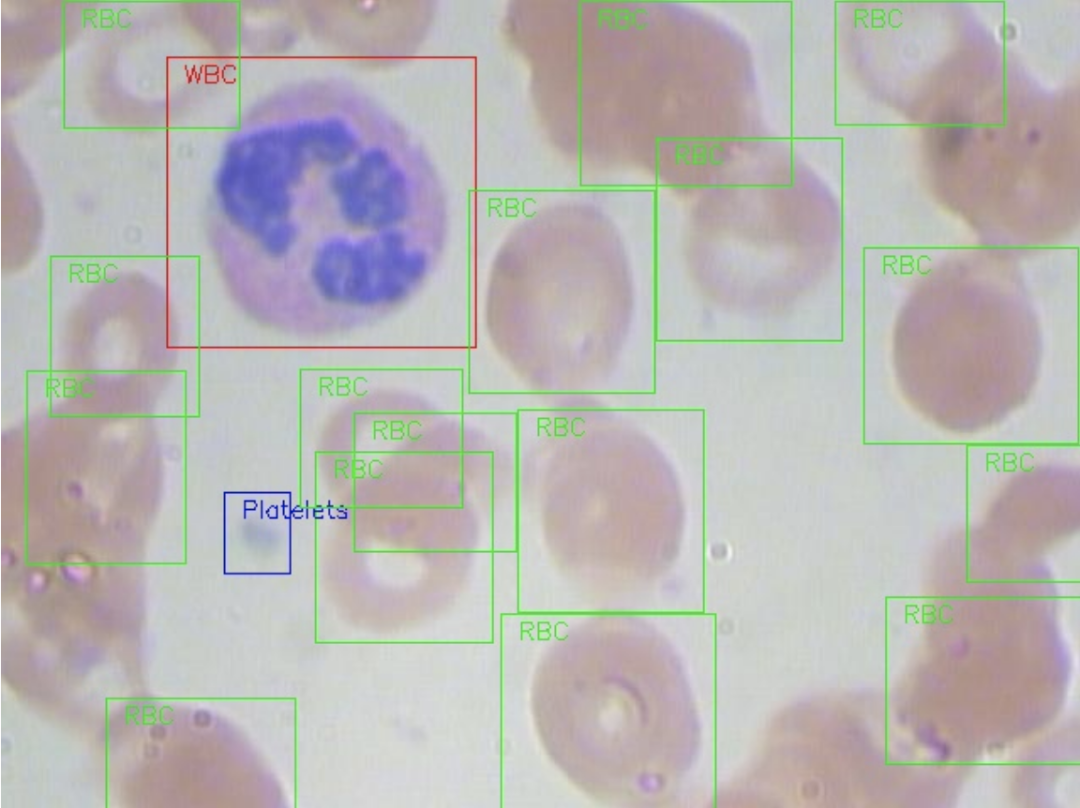

血细胞图像数据集

数据集下载地址:http://m6z.cn/5zdTDb

该数据集包含 12,500 张带有细胞类型标签 (CSV) 的增强血细胞图像 (JPEG)。4 种不同细胞类型中的每一种都有大约 3,000 张图像,这些图像被分组到 4 个不同的文件夹中(根据细胞类型)。细胞类型是嗜酸性粒细胞、淋巴细胞、单核细胞和中性粒细胞。